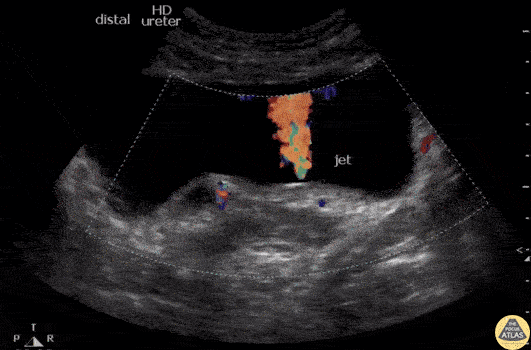

Transabdominal ultrasound showing right-sided twinkle artifact with strong left-sided urine jet indicative of right-sided UVJ stone obstruction. Image courtesy of Robert Jones DO, FACEP @RJonesSonoEM Director, Emergency Ultrasound; MetroHealth Medical Center; Professor, Case Western Reserve Medical School, Cleveland, OH View his original post here